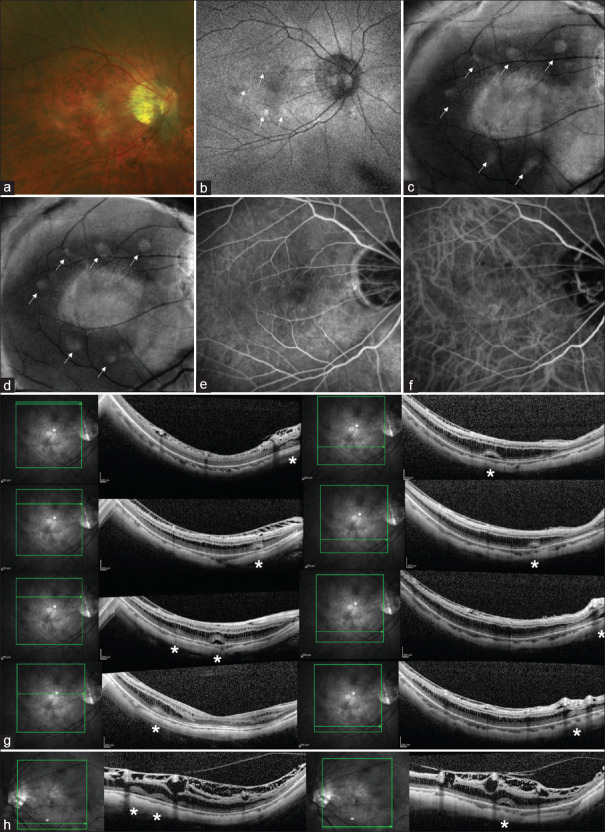

本研究探讨了近视牵拉性黄斑病变(MTM)中多发中央凹旁视网膜脱离(rd)的发生情况,强调了与通常观察到的中央凹脱离相比,非典型的中央凹外受累。患者1,46岁男性,表现为MTM伴视网膜裂和四个小视网膜下液(SRF)袋,位于中央窝下方,伴高自荧光卵黄样沉积物。患者2,43岁男性,报告左眼环状模糊视力,显示MTM,中央窝周围有六个稳定的SRF袋。在5年的随访期间,这些SRF袋的直径保持在173 - 1140微米的稳定大小。有趣的是,荧光素和吲哚菁血管造影均未显示渗漏或高渗透性。该研究强调了在MTM中全面探索中心外rd的必要性,挑战了传统的期望。这些与近视裂相关的持续的中央凹外脱离的机制尚不清楚。这些发现促使进一步研究揭示这种罕见现象的复杂机制,强调了扩大我们对MTM眼睛中凹外表现的理解的重要性。

This study investigates the occurrence of multiple parafoveal retinal detachments (RDs) in myopic traction maculopathy (MTM), emphasizing the atypical extrafoveal involvement compared to central foveal detachment commonly observed. Patient 1, a 46-year-old male, exhibited MTM with retinoschisis and four small subretinal fluid (SRF) pockets inferior to the fovea, accompanied by a hyperautofluorescent vitelliform deposit. Patient 2, a 43-year-old male, reported ring-shaped dim vision in the left eye, displaying MTM with six stable SRF pockets surrounding the fovea. These SRF pockets maintained a stable size ranging from 173 to 1140 um in diameter over the course of a 5-year follow-up period. Interestingly, fluorescein and indocyanine angiography showed no leakage or hyperpermeability in both cases. The study highlights the necessity for a comprehensive exploration of extrafoveal RDs in MTM, challenging conventional expectations. The mechanism of these persistent extrafoveal detachments associated with myopic schisis was unknown. The findings prompt further research to unravel the intricate mechanisms of this rarely reported phenomenon, emphasizing the importance of expanding our understanding of extrafoveal manifestations in eyes with MTM.